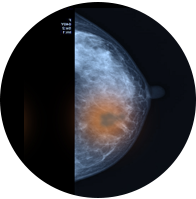

여성암 발생률 1~2위,

조기 발견 시 5년 생존율 98% img

유방암

유방암 조기 발견을 위해 정기적인 유방검진은 필수입니다!

유방암은 조기에 치료하면 완치율이 높습니다.

0기 유방암인 관상내피암의 경우 치료 후 5년 동안 생존할 가능성이 거의 100%에 가까우며,

혹의 크기가 2cm 이하이고 겨드랑이 임파선에 퍼지지 않은 경우(1기)에는 5년 생존율이 98% 정도로 매우 높습니다.